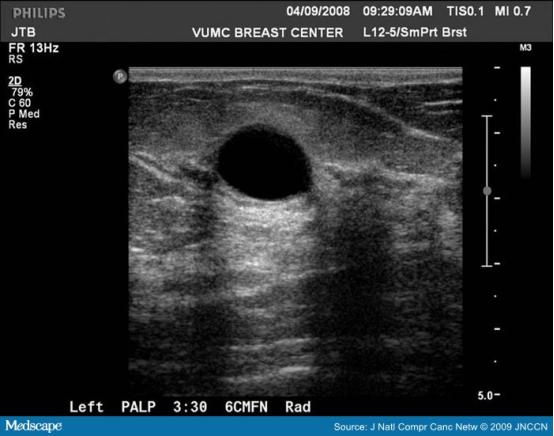

BI-RADS 4*级A**:可以触及的,边界清晰的肿物,超声可诊断为腺瘤以及可以触及的混合型囊肿,恶性可能在2-10%范围;

BI-RADS 4*级A**